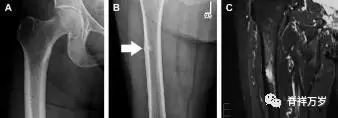

非典型股骨骨折

另一种易漏诊的骨折是非典型股骨骨折,这种骨折与长期服用双膦酸盐相关,常发生在使用双膦酸盐 3 年以上的患者。前驱症状表现为腹股沟痛或大腿痛的患者中,60%~70% 被错误地认为由腰背痛或髋关节炎引起。

这种骨折的一个典型表现为火山口状骨膜隆起及一横行透亮带。值得注意的是,超过 50% 的患者表现为股骨干完全骨折。由于 50%~60% 的患者会累及双侧,所以一旦一侧下肢确诊,需行对侧下肢检查。

图 9 老年患者长期服用双磷酸盐引起的骨折。A 髋部正位片,箭头所示,股骨外侧皮质存在横行透亮带。B 后续的股骨 X 线片示局灶性骨膜反应,以及此类骨折的特征性表现-火山口状骨膜隆起(箭头)。C MRI 冠状位 STIR 序列扫描示相应骨折平面的骨髓水肿表现